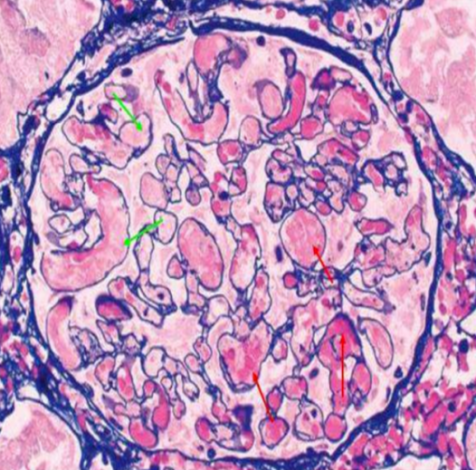

肾穿刺活检结果“一锤定音”,通过光学显微镜(光镜)和电子显微镜(电镜)再次明确诊断,均证实了肾内血栓性微血管疾病的特征性改变。李女士最终被明确诊断为非典型溶血性尿毒综合征(aHUS)。

TMA急性期典型的肾小球改变